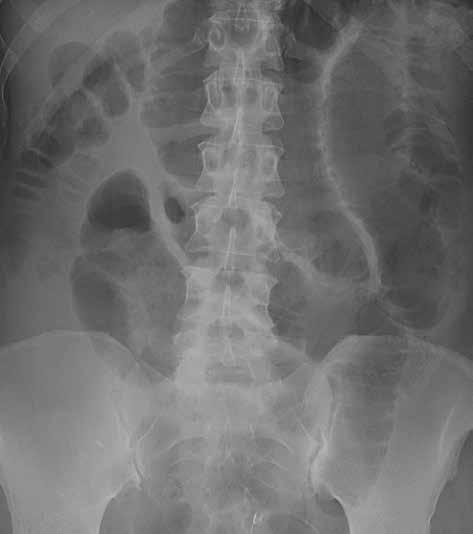

Prostý snímek břicha je stále jednou z nejlevnějších a nejdostupnějších zobrazovacích metod, využívaných při vyšetření nemocných s náhlou příhodou břišní. I když jeho význam klesá a dnes toto vyšetření nelze považovat za „metodu první volby“, má přesto i v době výpočetní tomografie (CT), ultrazvuku (UZ) a MR (magnetické rezonance) využití při podezření na střevní obstrukci či perforaci trávicí trubice, při hodnocení polohy drénů nebo detekci rentgenkontrastního tělesa (obr. 1).

Můžeme provést předozadní snímek vleže na zádech a/nebo zadopřední snímek vestoje v závislosti na indikaci vyšetření. U nemocných ve vážném stavu lze snímkování provádět přímo na lůžku, ovšem za cenu jeho nižší kvality. Prostý snímek břicha vleže na zádech má větší výpovědní hodnotu a standardně i vyšší kvalitu. Přesněji na něm můžeme posoudit šířku lumen tenkého i tlustého střeva. Vzduch tvoří negativní kontrast, který umožní částečně hodnotit šíři střevní stěny i řas. Lépe než u snímku vestoje lze také zhodnotit rozložení plynné náplně střev, a tím i snáze lokalizovat přechodové zóny (obr. 2).